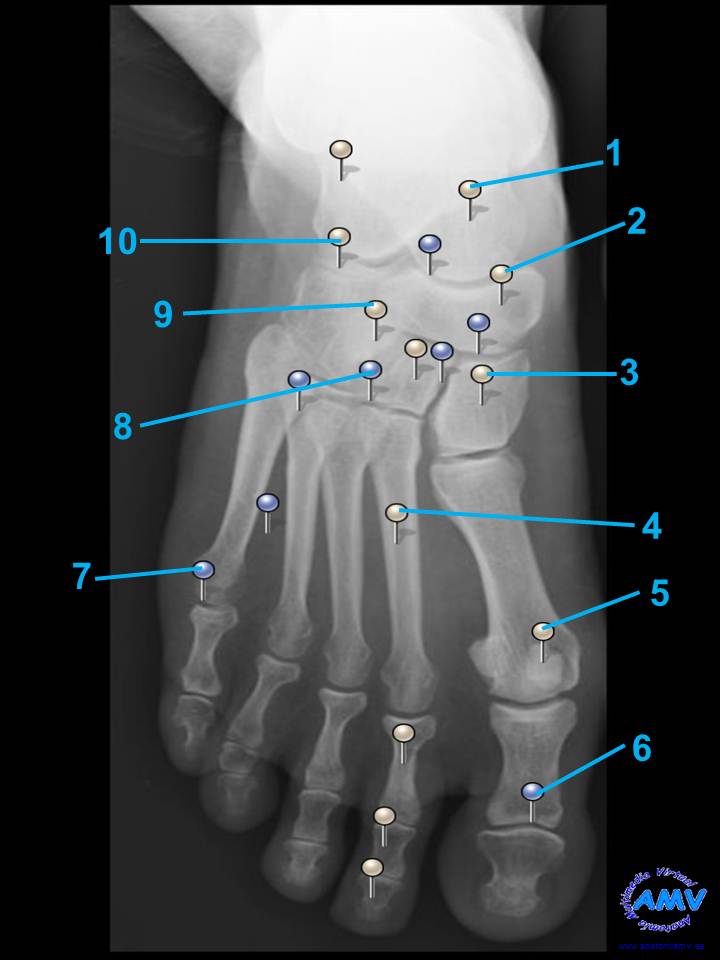

rx_mi_10.jpgIndique que estructura se señala con el número correspondiente:

El nº 1 señala .

El nº 2 señala .

El nº 3 señala .

El nº 4 señala .

El nº 5 señala .

El nº 6 señala .

El nº 7 señala .

El nº 8 señala .

El nº 9 señala .

El nº 10 señala .